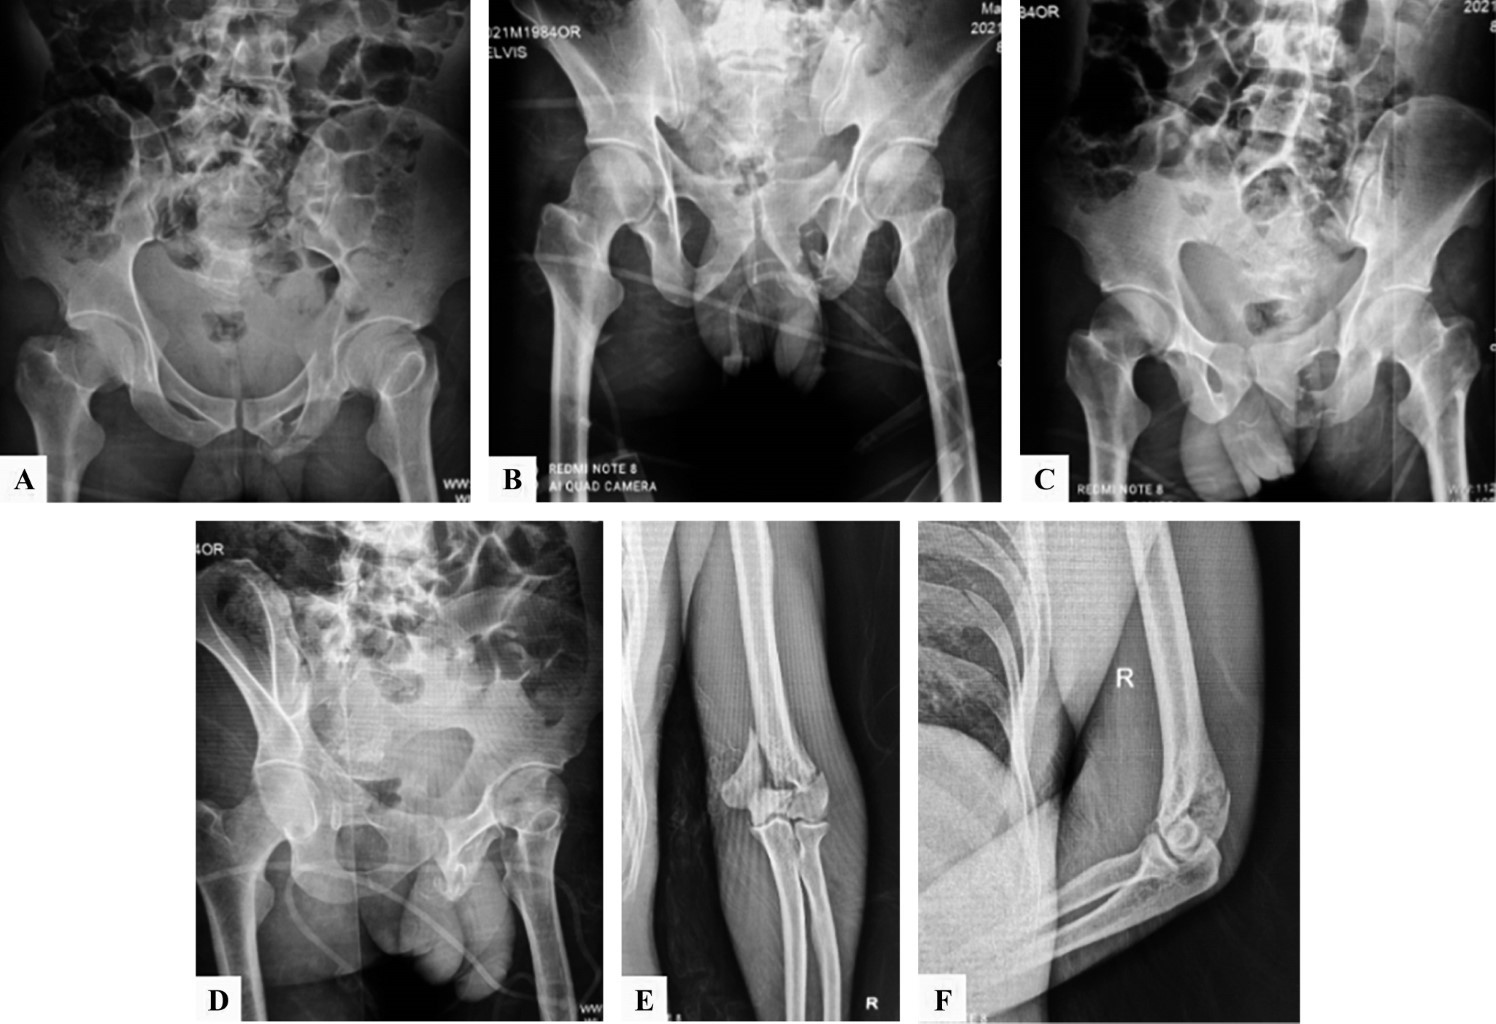

Se realizan radiografías de control serie pélvica y radiografías de codo y columna (Figura 2). En estas series se evidencian disrupción del anillo pélvico anterior del lado izquierdo, fractura articular de húmero, con fractura en arcos costales cinco y seis; serie radiográfica de Judet. Posteriormente se realizan tomografía axial computarizada (TAC) con cortes axiales sagitales y coronales de columna con pelvis (Figura 3) y reconstrucción 3D (Figura 4) donde se observa fractura del anillo pélvico tipo C de Tile por mecanismo de cizallamiento vertical en donde se observan fracturas de rama iliopubiana en zona III de Nakatani e isquiática ipsilateral izquierdas con fractura multifragmentada de sacro con patrón H asociada a hundimiento de plataforma de S1 y fracturas transforaminales bilaterales que se unen a nivel de S2-S3 clasificada como C3 por AO. Se encuentran también fracturas de los cuerpos vertebrales que fueron clasificadas acorde con la propuesta de AO, L1 por compresión tipo A4, fractura de L5 por distracción tipo B2 además de fracturas de las apófisis transversas de L4, L3 y L2 secundarias al cizallamiento vertical tipo A0.

El paciente evoluciona sin infección y con cicatrización completa de las heridas sin sufrimiento cutáneo. El seguimiento del paciente a la actualidad muestra progresión en la consolidación de las fracturas del anillo pélvico y columna a los tres meses de evolución sin colapso de los cuerpos vertebrales ni cizallamiento del sacro sobre los ilíacos, el paciente recuperó la función de la marcha adecuadamente, con mejoría en la sensibilidad completa; se recomienda el retiro de implantes de la columna vertebral para lograr el máximo beneficio.

Actualmente el paciente es capaz de deambular autónomamente sólo con necesidad de bastón. Refiere no presentar dolor en la cadera que interfiera con sus actividades con un Harris hip score de 43. Refiere dolor tolerable en región lumbar, sin que este sea incapacitante. Se anexan fotos actuales de su estado postquirúrgico (Figura 8).